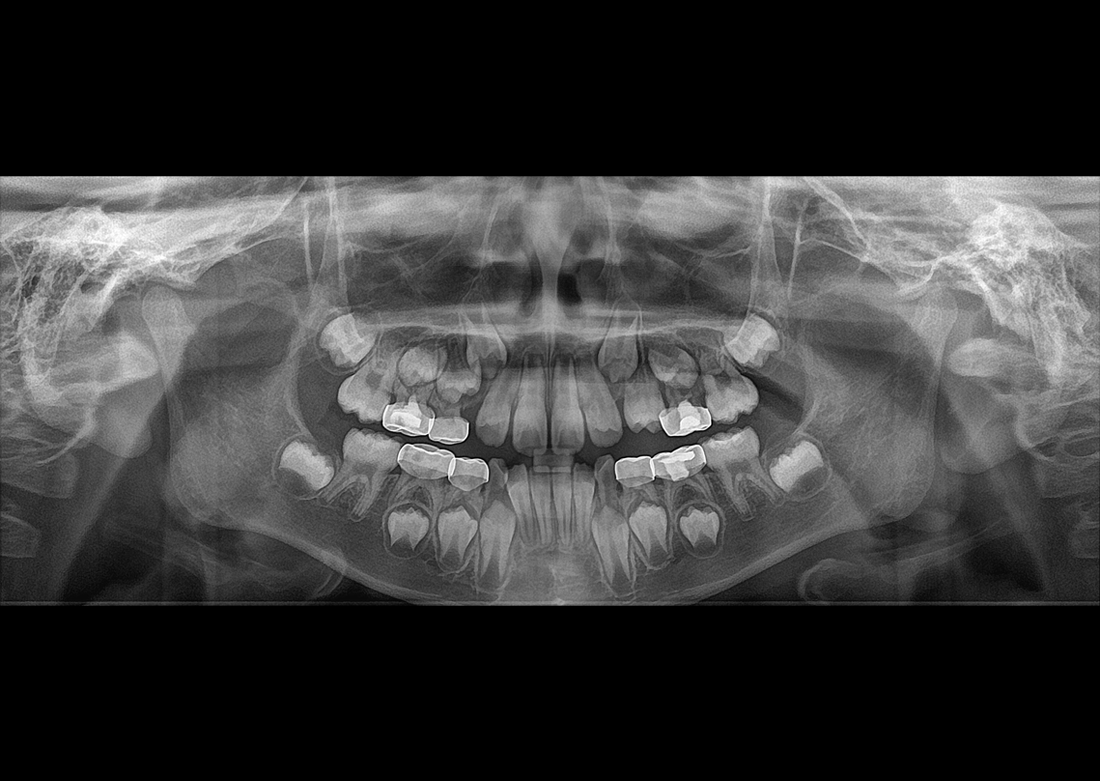

KLİNIKAI KÉPEK

Kiváló diagnosztikai képalkotás több éves tapasztalattal és szakértelemmel.

A Genoray büszkesége, amelyet világszerte elismernek és szeretnek.